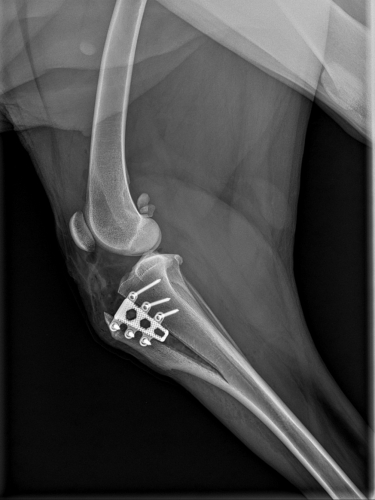

Heute Kontrolluntersuchung zur vollsten Zufriedenheit unserer Tierärztin absolviert. Wenn man das Röntgenbild sieht, wird sofort klar, warum nun für 6 Wochen kurze Leine verordnet ist. Da muß so einiges zusammenwachsen und ausheilen. Der Knochen wurde gespalten und langsam aufgedehnt, damit die Patellarsehne das Kreuzband ersetzen kann, und das Teil, welches fast aussieht, wie eine Haarspange, wurde dazwischen gesetzt. Der Plan ist, daß der Spalt bald wieder zu wächst.